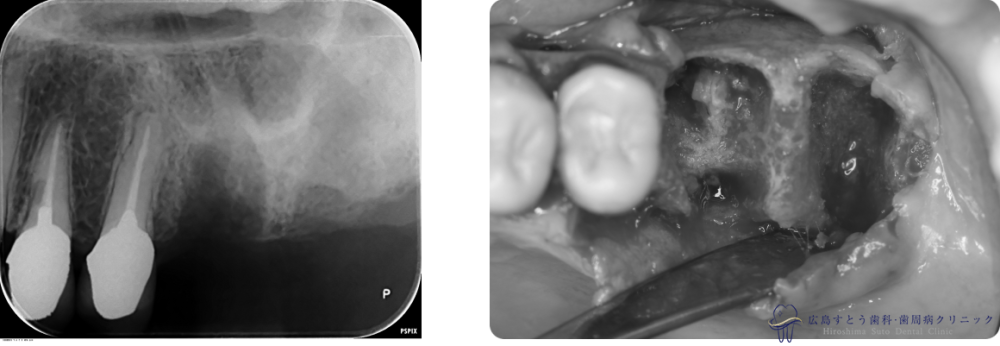

Case2

Before

初診時:左上の第一、第二大臼歯は歯根が破折しており、抜歯することになりました。

初診時:左上の第一、第二大臼歯は歯根が破折しており、抜歯することになりました。

術中

抜歯後の状態

手術中の写真

手術直後のレントゲン

6ヶ月後のレントゲン写真

| 治療名 | GBR(骨再生誘導療法)、インプラント治療(2本分) |

|---|---|

| 治療説明 | 左上の奥歯に歯茎の腫れがあり、診査の結果歯根が破折しておりました。抜歯後はインプラント治療を希望されたため、抜歯後、失われた歯槽骨を増生するためにGBRを行い、インプラント治療を行いました。 |

| 治療回数・期間 | 約10ヶ月(歯周基本治療、抜歯、GBR、インプラント治療) |

| 副作用とリスク | 歯周外科後には一時的に術後に腫れや仏痛や出血が発現することがあります。 治癒の状態によって治療期間が長くかかる場合があります。 |

| 料金 | 104.5万円 |